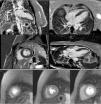

Cardiac magnetic resonance imaging (MRI), performed six days after admission, showed mild hypokinesia of the mid segments of both anterior and anteroseptal walls, preserved global LV systolic function, and diffuse myocardial edema (Figure 5), with no significant late enhancement and no perfusion defects (Figure 6), which was a clue to the diagnosis of Takotsubo cardiomyopathy.

Figure 5.

Cardiac magnetic resonance imaging cine sequences (a) showing mild hypokinesia of the mid segments of both anterior and anteroseptal walls and preserved global left ventricular systolic function; (b) T2-weighted short tau inversion recovery sequence revealing diffuse myocardial edema.

Figure 6.

Cardiac magnetic resonance imaging, contrast-enhanced sequences with gadolinium (a) and perfusion sequences (b), showing no significant late enhancement and no perfusion defects.